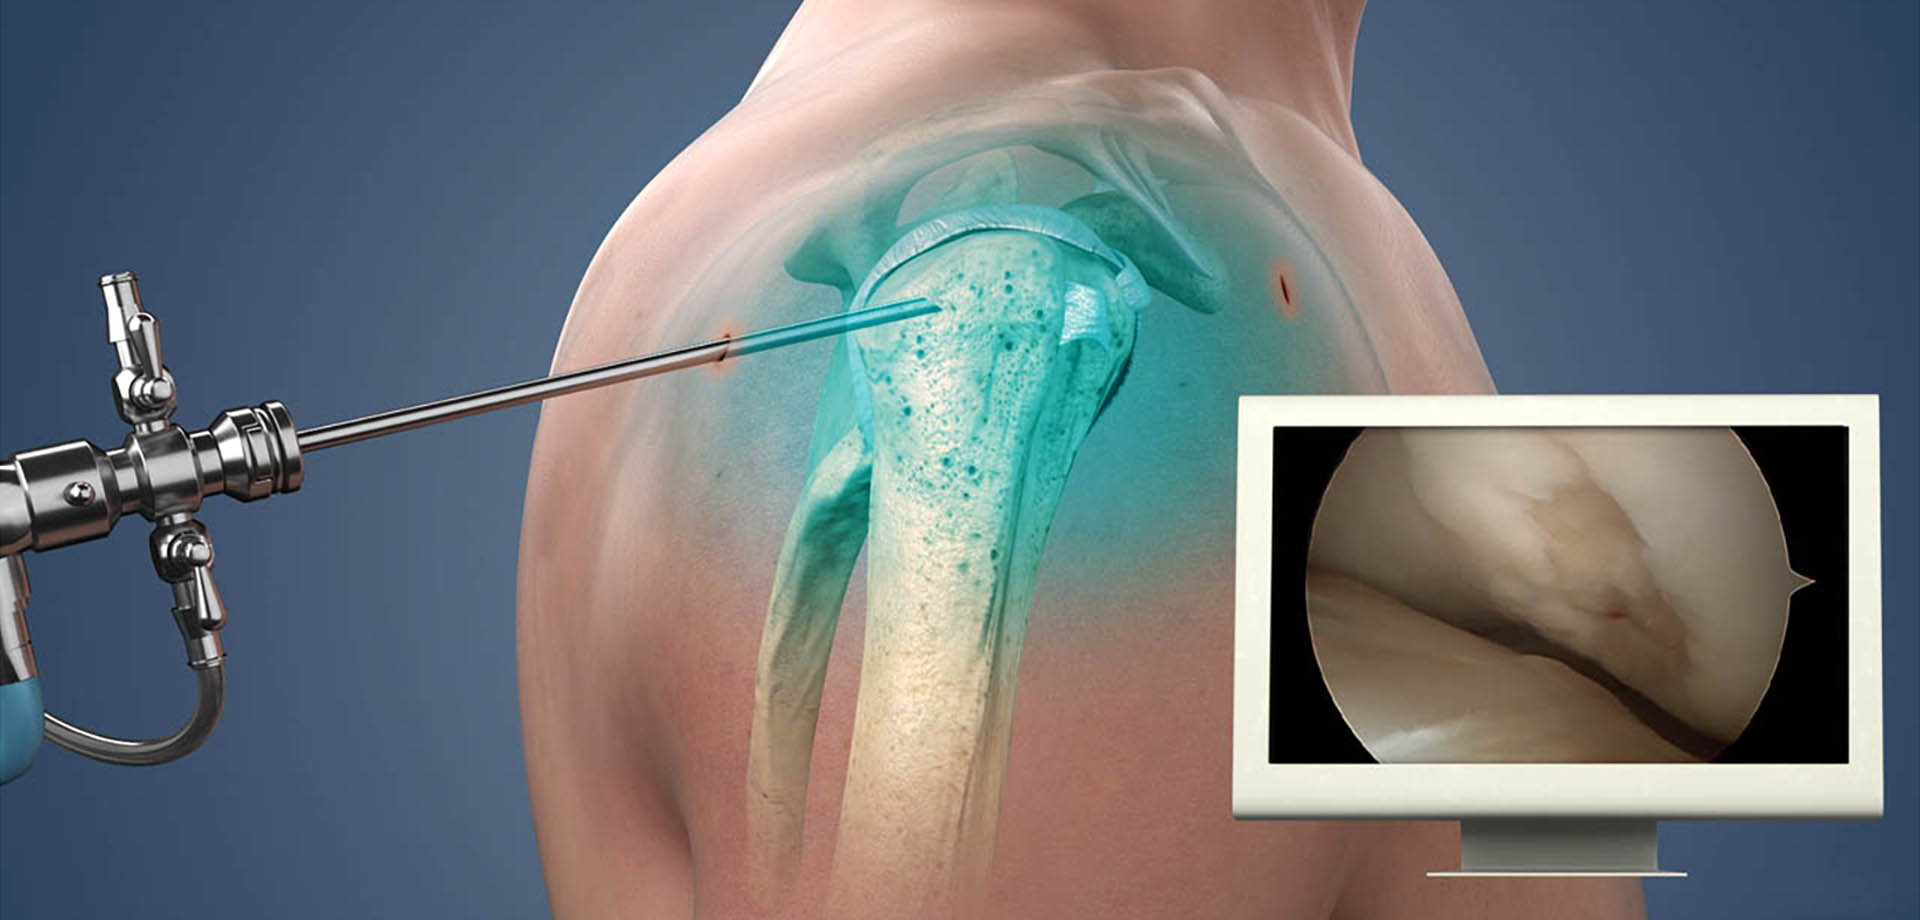

The department offers a full spectrum of non-surgical and surgical orthopedic services, with a strong emphasis on minimally invasive techniques. Advanced procedures such as arthroscopy, minimally invasive and endoscopic spine interventions, and modern fracture fixation methods are used to reduce surgical trauma, minimize pain, and promote faster recovery with shorter hospital stays. These approaches allow patients to return to daily activities and work more quickly, while maintaining high standards of safety and clinical outcomes.

Sports medicine is an integral component of the department’s services. We manage acute injuries, overuse conditions, and degenerative joint problems commonly seen in athletes and physically active individuals. Conditions involving the knee, shoulder, ankle, hip, and spine are treated through a coordinated approach that combines medical management, targeted rehabilitation, and, when necessary, surgical intervention. Rehabilitation programs are carefully structured to restore strength, flexibility, balance, and performance while reducing the risk of re-injury.

- Shoulder Impingement Syndrome

- Frozen Shoulder (Adhesive Capsulitis)